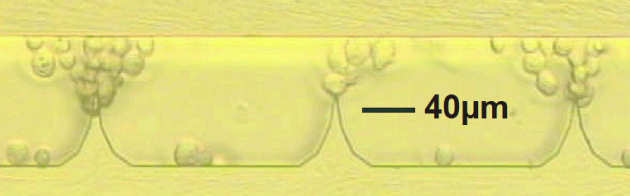

We have developed a fixed microelectrode device for cell stimulation using micro-electro-mechanical systems (MEMS) technology. Dielectrophoretic forces obtained from non-uniform electric fields are used for manipulating and positioning osteoblasts. The experiments show that the osteoblasts experience positive dielectrophoresis (p-DEP) when suspended in iso-osmotic culture medium and exposed to AC fields at 5 MHz frequency. Negative dielectrophoresis (n-DEP) is obtained at 0.1 MHz. The viability of osteoblasts under dielectrophoresis has been investigated. The viability values for cells exposed to DEP are nearly three times higher than the control values, indicating that dielectrophoresis may have an anabolic effect on osteoblasts.

| Prototype dielectrophoretic stimulation device fabricated in BSOI |

| Osteoblasts concentrated near shaped electrodes by DEP force |